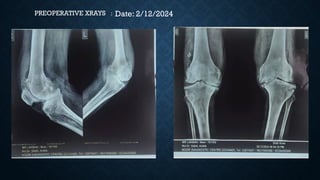

RADIOGRAPHS

• Joint space reduction

• Sclerosis

• Osteophytes

• Poor bone quality

Tibia Laterally

displaced b/l

Mechanical axis

medially displaced

Date: 2/12/2024

PREOPERATIVE XRAYS :

KELLEGREN-LAWRENCE

GRADE-4-

Large Osteophytes,marked

narrowing of joint

space,severe sclerosis and

definite deformity of bone

contour.